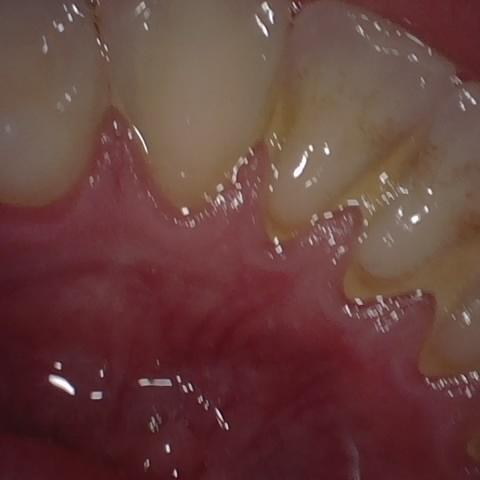

Annotated as "Good"